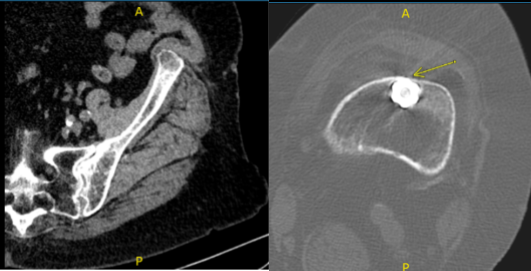

After 6 weeks from the first visit, the patient returned with a CT scan result, it was reviewed and ruled out our impingement, and there were mild degenerative changes of the left hip and presents atherosclerotic disease.

Also found that the distal tip of the femur impinging on the anterior cortex of the femur with erosion. We discussed treatment options including operative and nonoperative treatment.

Patient returned to the office for post operative follow up. She presented the result of her CT scan, 4 weeks after the operation and there are mild osteoarthritic degenerative changes.